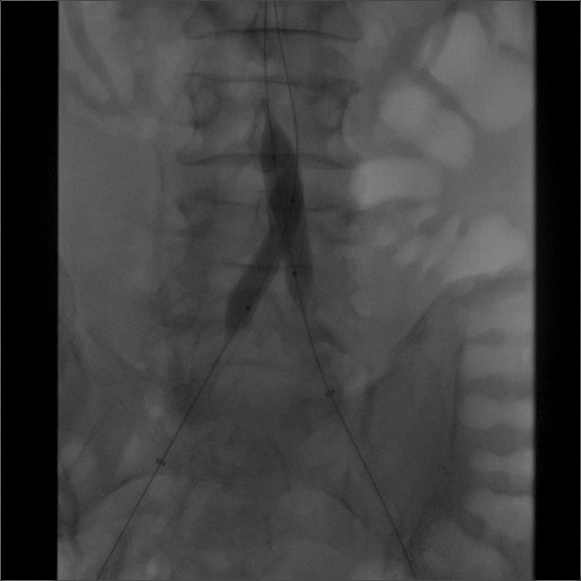

(5) 行双侧髂总动脉“对吻”支架植入术,并双侧导入INVETEC 12*40mm行双侧髂总动脉支架内近端行球囊扩张。

导丝怎么扩【问术ASK】佟铸教授:双侧髂总动脉“对吻”球扩覆膜支架植入术_https://www.jmylbn.com_新闻资讯_第7张

(6) 最后造影示,双侧髂总动脉及远端髂动脉通畅,支架张开充分,贴壁良好,位置理想,无造影及外溢。远端造影未见栓塞。